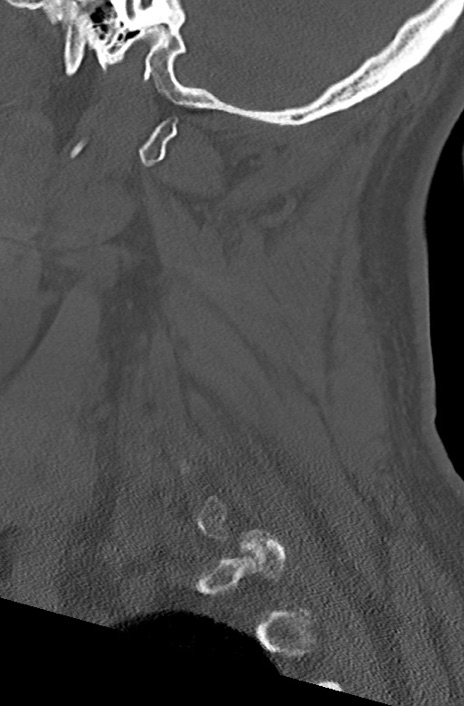

頚椎CT

矢状断像と横断像